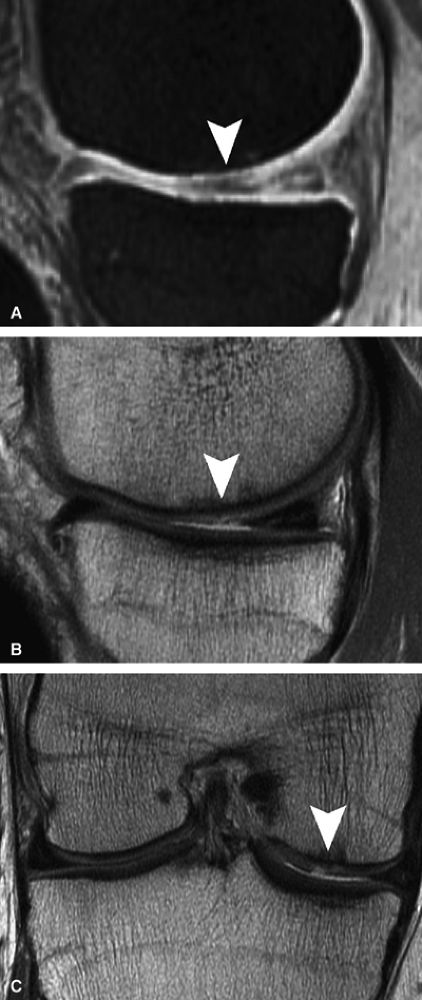

FIGURE 7.6 ● (A) Sagittal fat-suppressed T1-weighted gradient-echo MR image sequence of the knee demonstrates a focal high-grade partial-thickness cartilage defect overlying the medial femoral condyle (arrowheads). In the equivalent time required to acquire this single pulse sequence, cartilage-sensitive fast spin-echo MR sequences in two planes—sagittal (B) and coronal (C)—can be obtained, in which the depth of the lesion is much better delineated. (Reprinted by permission of SAGE Publications, Inc., from Am J Sports Med, in press.)

FIGURE 7.18 ● Prospective MR evaluation of a bone bruise in the knee of a 28-year-old man with a complete ACL tear. Sagittal fat-suppressed (A) and fast spin-echo (B) MR images obtained at the time of injury demonstrate characteristic bone marrow edema with compression of cartilage over the lateral femoral condyle (white arrow). A sagittal MR image obtained 19 months later (C) demonstrates proud subchondral bone with focal cartilage loss over the condyle (black arrow), as well as flap formation over the tibial plateau (arrowhead). (Reprinted by permission of SAGE Publications, Inc., from Am J Sports Med, in press.)